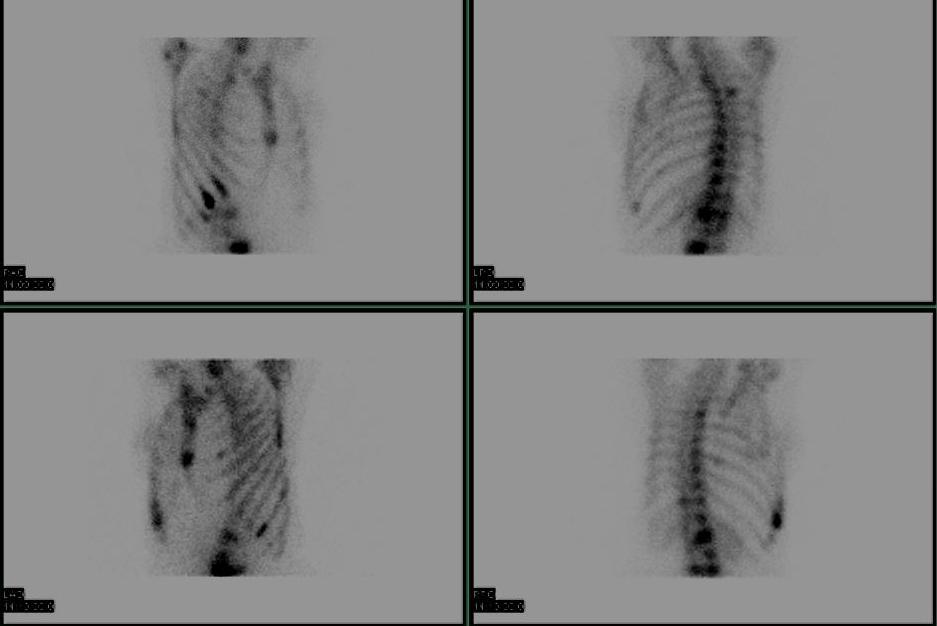

SPECT (Single photon emission CT)

Tomographic examination

- rotate gamma camera around the patient

- creates CT like slice

- useful in spine i.e. spondylysis